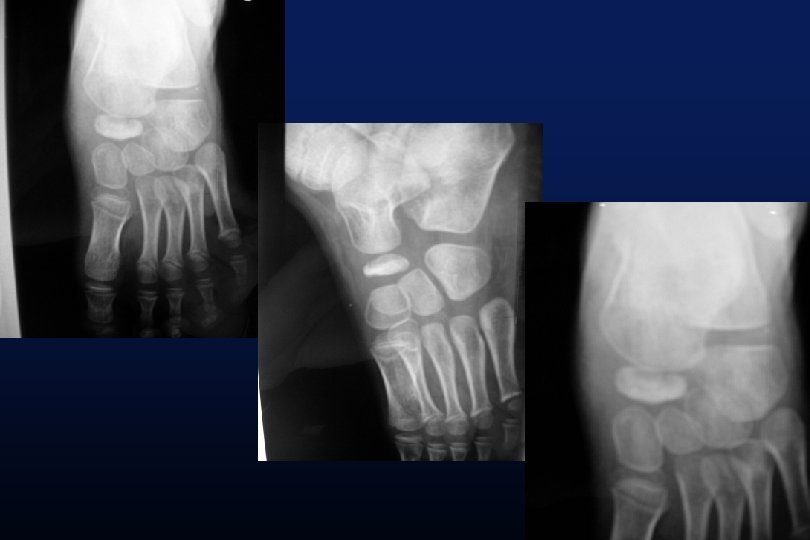

LES SYNOSTOSES DE L ’ARRIERE PIED Coalitions Tarsiennes (Tarsal Coalitions)

CALCANEO NAVICULAIRES (60%) TALO CALCANEENNES Synostoses et coalitions tarsiennes chez l'enfant. Étude de 68 cas chez 47 patients Ph. Rouvreau, J. C. Pouliquen, J. Langlais, C. Glorion, G. de Cerqueira Daltro The Too-Long Anterior Process Calcaneus: A Report of 39 Cases in 25 Children and Adolescents Pouliquen, J. C. M. D. ; Duranthon, L. D. M. D. ; Glorion, Ch. M. D. ; Kassis, B. Journal of Pediatric Orthopaedics Volume 18(3) June 1998 333 -336